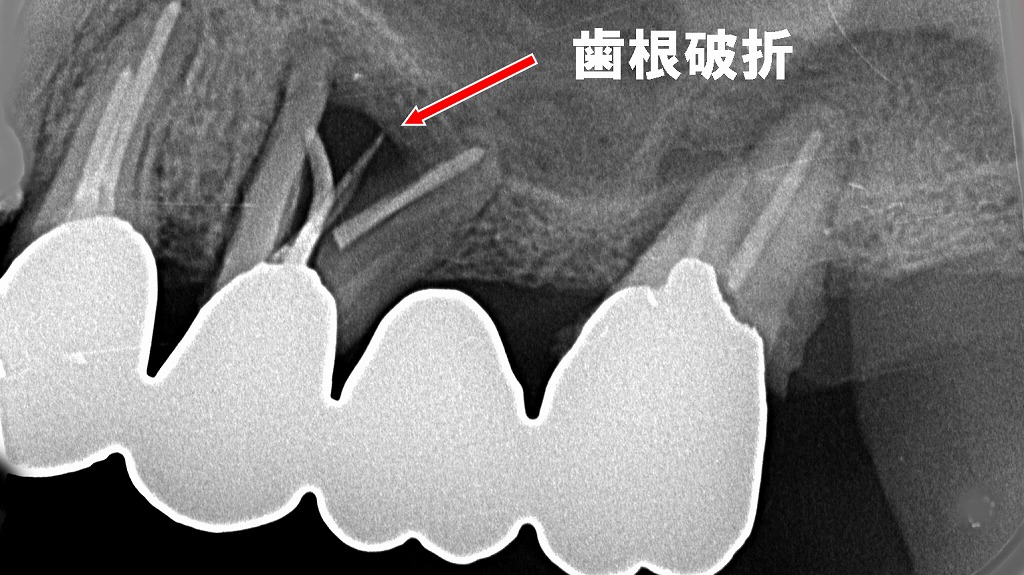

💥3. 歯根破折(Vertical Root Fracture)

歯根が縦方向に破折した場合、細菌感染が歯根膜全体へ拡大するため保存は極めて困難です。

- 🔍 視診では診断困難

- 📸 レントゲンやCBCTで確認

- 🧩 接着修復はほぼ不可能

👉 支台歯として使用されている場合でも、破折が確認された時点で抜歯適応となります。